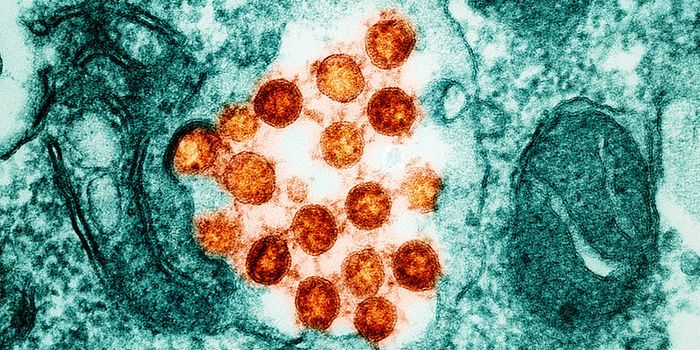

MAR 28, 2024Clinical & Molecular DXBorna disease virus (BoDV-1) has long caused fatal encephalitis, Borna virus disease in horses and sheep in Central Euro ...